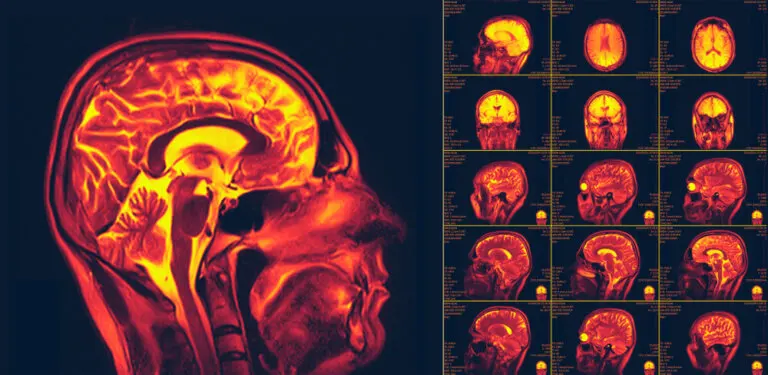

Así, se empezaron a realizar diferentes pruebas de imágenes y estimulación con las que se consiguió poner de manifiesto la existencia de la neuroplasticidad. Actualmente, todavía se están investigando todos los mecanismos que intervienen en este proceso, tal y como podemos observar en la investigación citada anteriormente.